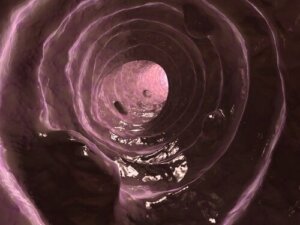

Lima on suolen limakalvon erittämää ainetta – samanlaista kuin hengitysteiden epiteelin tuottama lima – jonka tehtävänä on pitää paksusuolen limakalvo voideltuna ja kosteana.